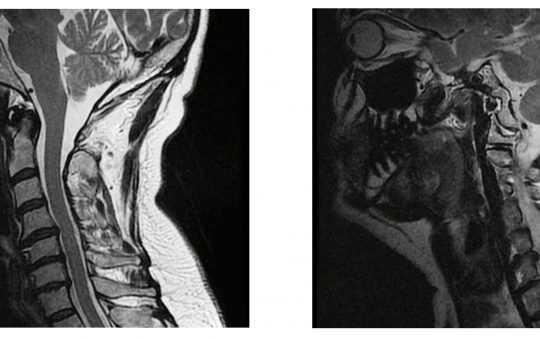

Preoperatorio

El resultado de la exploración objetiva refleja inflamación del tendón supraespinoso con anomalía en la rotación y lesión parcial de labrum. Por otro lado, la resonancia de columna cervical nos muestra tres hernias discales cervicales y cambios degenerativos en los niveles C4-C5, C5-C6 Y C6-C7.